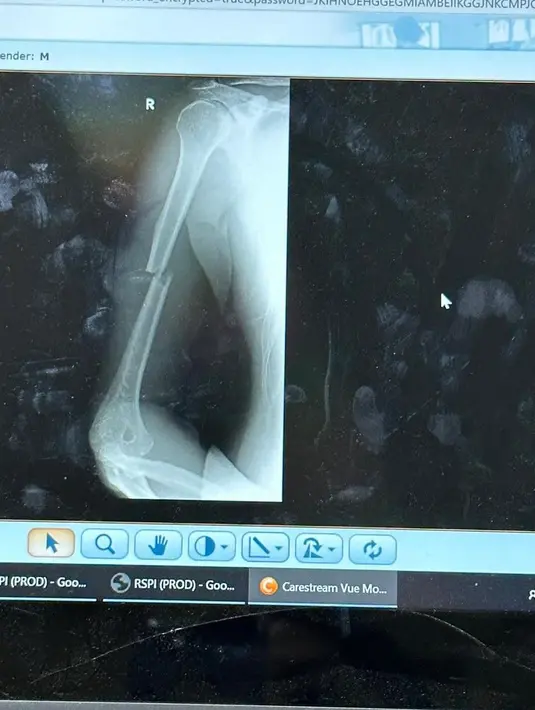

Perempuan seorang anak itu melihat proses pemulihan cukup cepat. Tapi terkadang masih merasakan sakit. Akibat terjatuh dari kuda, Irwansyah harus pasang pen di tangannya karena tulang patah. [Instagram/irwansyah_15]

"Progresnya cepet banget cuma masih sakit. Kadang-kadang suka ngilu. Namanya dipasang pen kan. Terus patahnya yang bener-bener misah. Jadi harus disambung pakai pen," kata Zaskia Sungkar dilansir dari kanal Cumicumi. [Instagram/irwansyah_15]